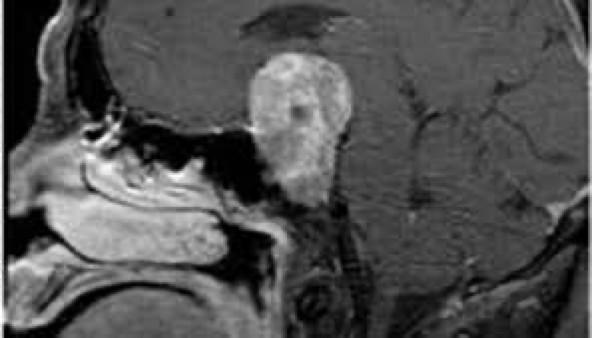

RMN DE HIPÓFISE: ADENOMA HIPOFISÁRIO